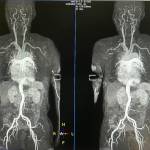

МРТ сердца является одним из наиболее сложных разделов современной медицины с точки зрения трудоемкости и техники выполнения, высочайших требований к аппаратному и программному обеспечению МР-сканера, длительной подготовки соответствующего квалифицированного персонала.

Основная тема мастер-класса: «МРТ картирование сердца (MR-mapping) как новый, современный и достоверный инструмент тканевой характеристики миокарда». Подробно рассмотрены методические приемы выполнения и принципы интерпретации при гипертрофической и дилатационной кардиомиопатиях, аритмогенной дисплазии правого желудочка, амилоидозе, кардиотоксическом поражении сердца при химиотерапии у онкологических пациентов, болезни Александера-Фабри, синдроме Такацубо, талассемиях и др. Проведен детальный разбор наиболее сложных диагностических случаев.